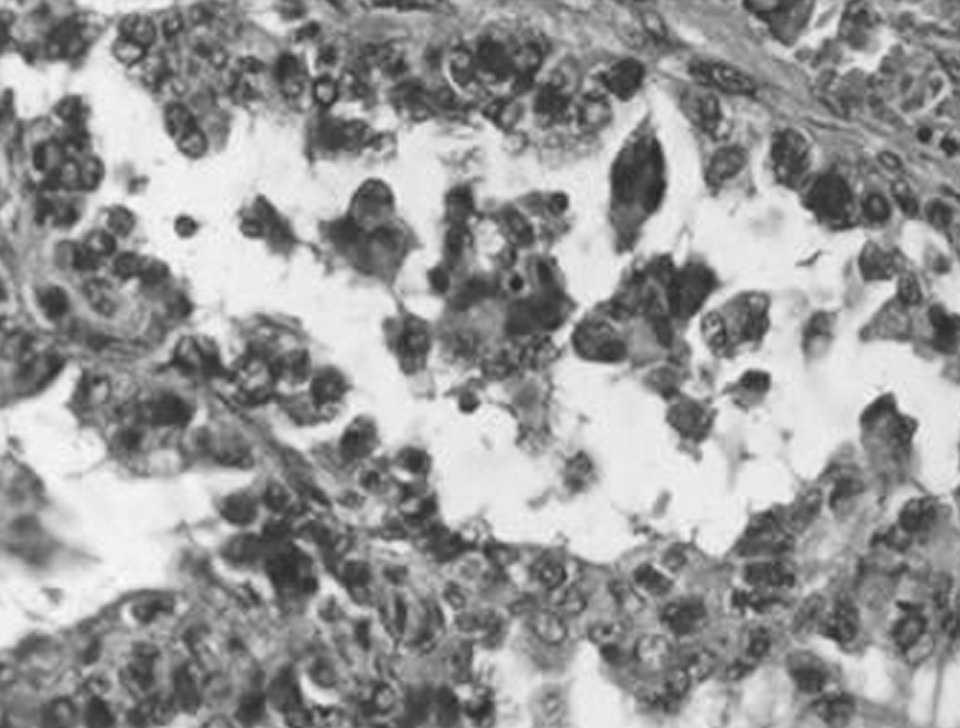

Microscópicamente se observó una tumoración constituida por canales vasculares, en ocasiones anastomosados, tapizados por células con una marcada atipia citológica y presencia de figuras de mitosis (CD34, factor VIII y vimentina positivas); también se observaron áreas sólidas, áreas papilares, así como abundantes áreas hemorrágicas y de necrosis. También se observaron metástasis hepáticas e incluso en el bazo supernumerario.

Fig. 4. Canales vasculares irregulares tapizados por células endoteliales atípicas.